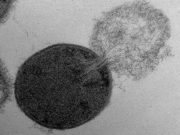

Nanometrik ölçekte ölüm: Antibakteriyellerin hücre duvarında açtıkları delikler ölçüldü

Antibiyotiklere karşı dirençli bakterilerin artması geleneksel antibiyotiklere alternatif arayışını başlattı. Bu alternatiflerden biri olan PlyC enzimi, streptokok boğaz ağrısı ve streptokokal şok sendromuna neden olan bakteriyi öldürüyor. Bu enzim bakterinin hücre duvarına kenetlendikten sonra bakteri duvarında bir delik oluşturuyor. Bu delik bakteri iç zarının dışarı çıkmasına sebep oluyor ve sonuç olarak hücrenin patlayıp ölmesine neden […]